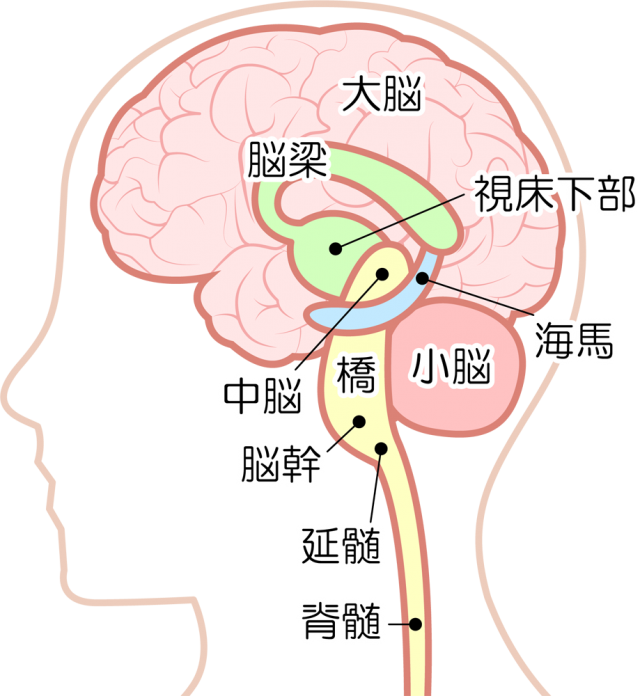

脳 脳幹 大脳 小脳 のしくみや働きがすぐわかる 高次脳機能障害の全て

間脳とは 働きや機能が障害された場合の症状についてのまとめ 人間ドックの評判とホントのところ

高校生物 間脳の構造と働き 映像授業のtry It トライイット

延髄